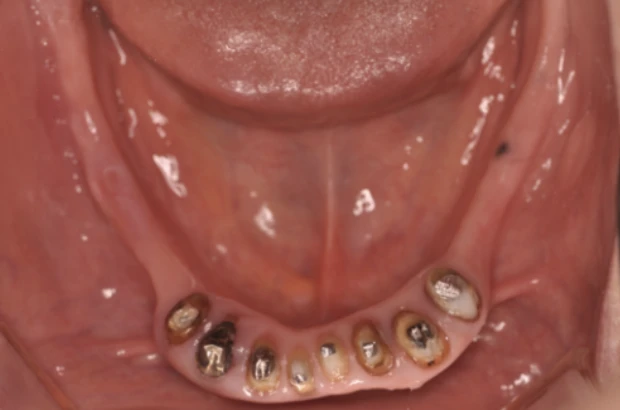

症状を詳しく見る: 症例7

主 訴

何度か入れ歯を作りなおしたが合わない

治療期間

24ヶ月

治療内容

インプラント7本、上顎自費義歯、セラミックCK8本

費 用

3,020,000円